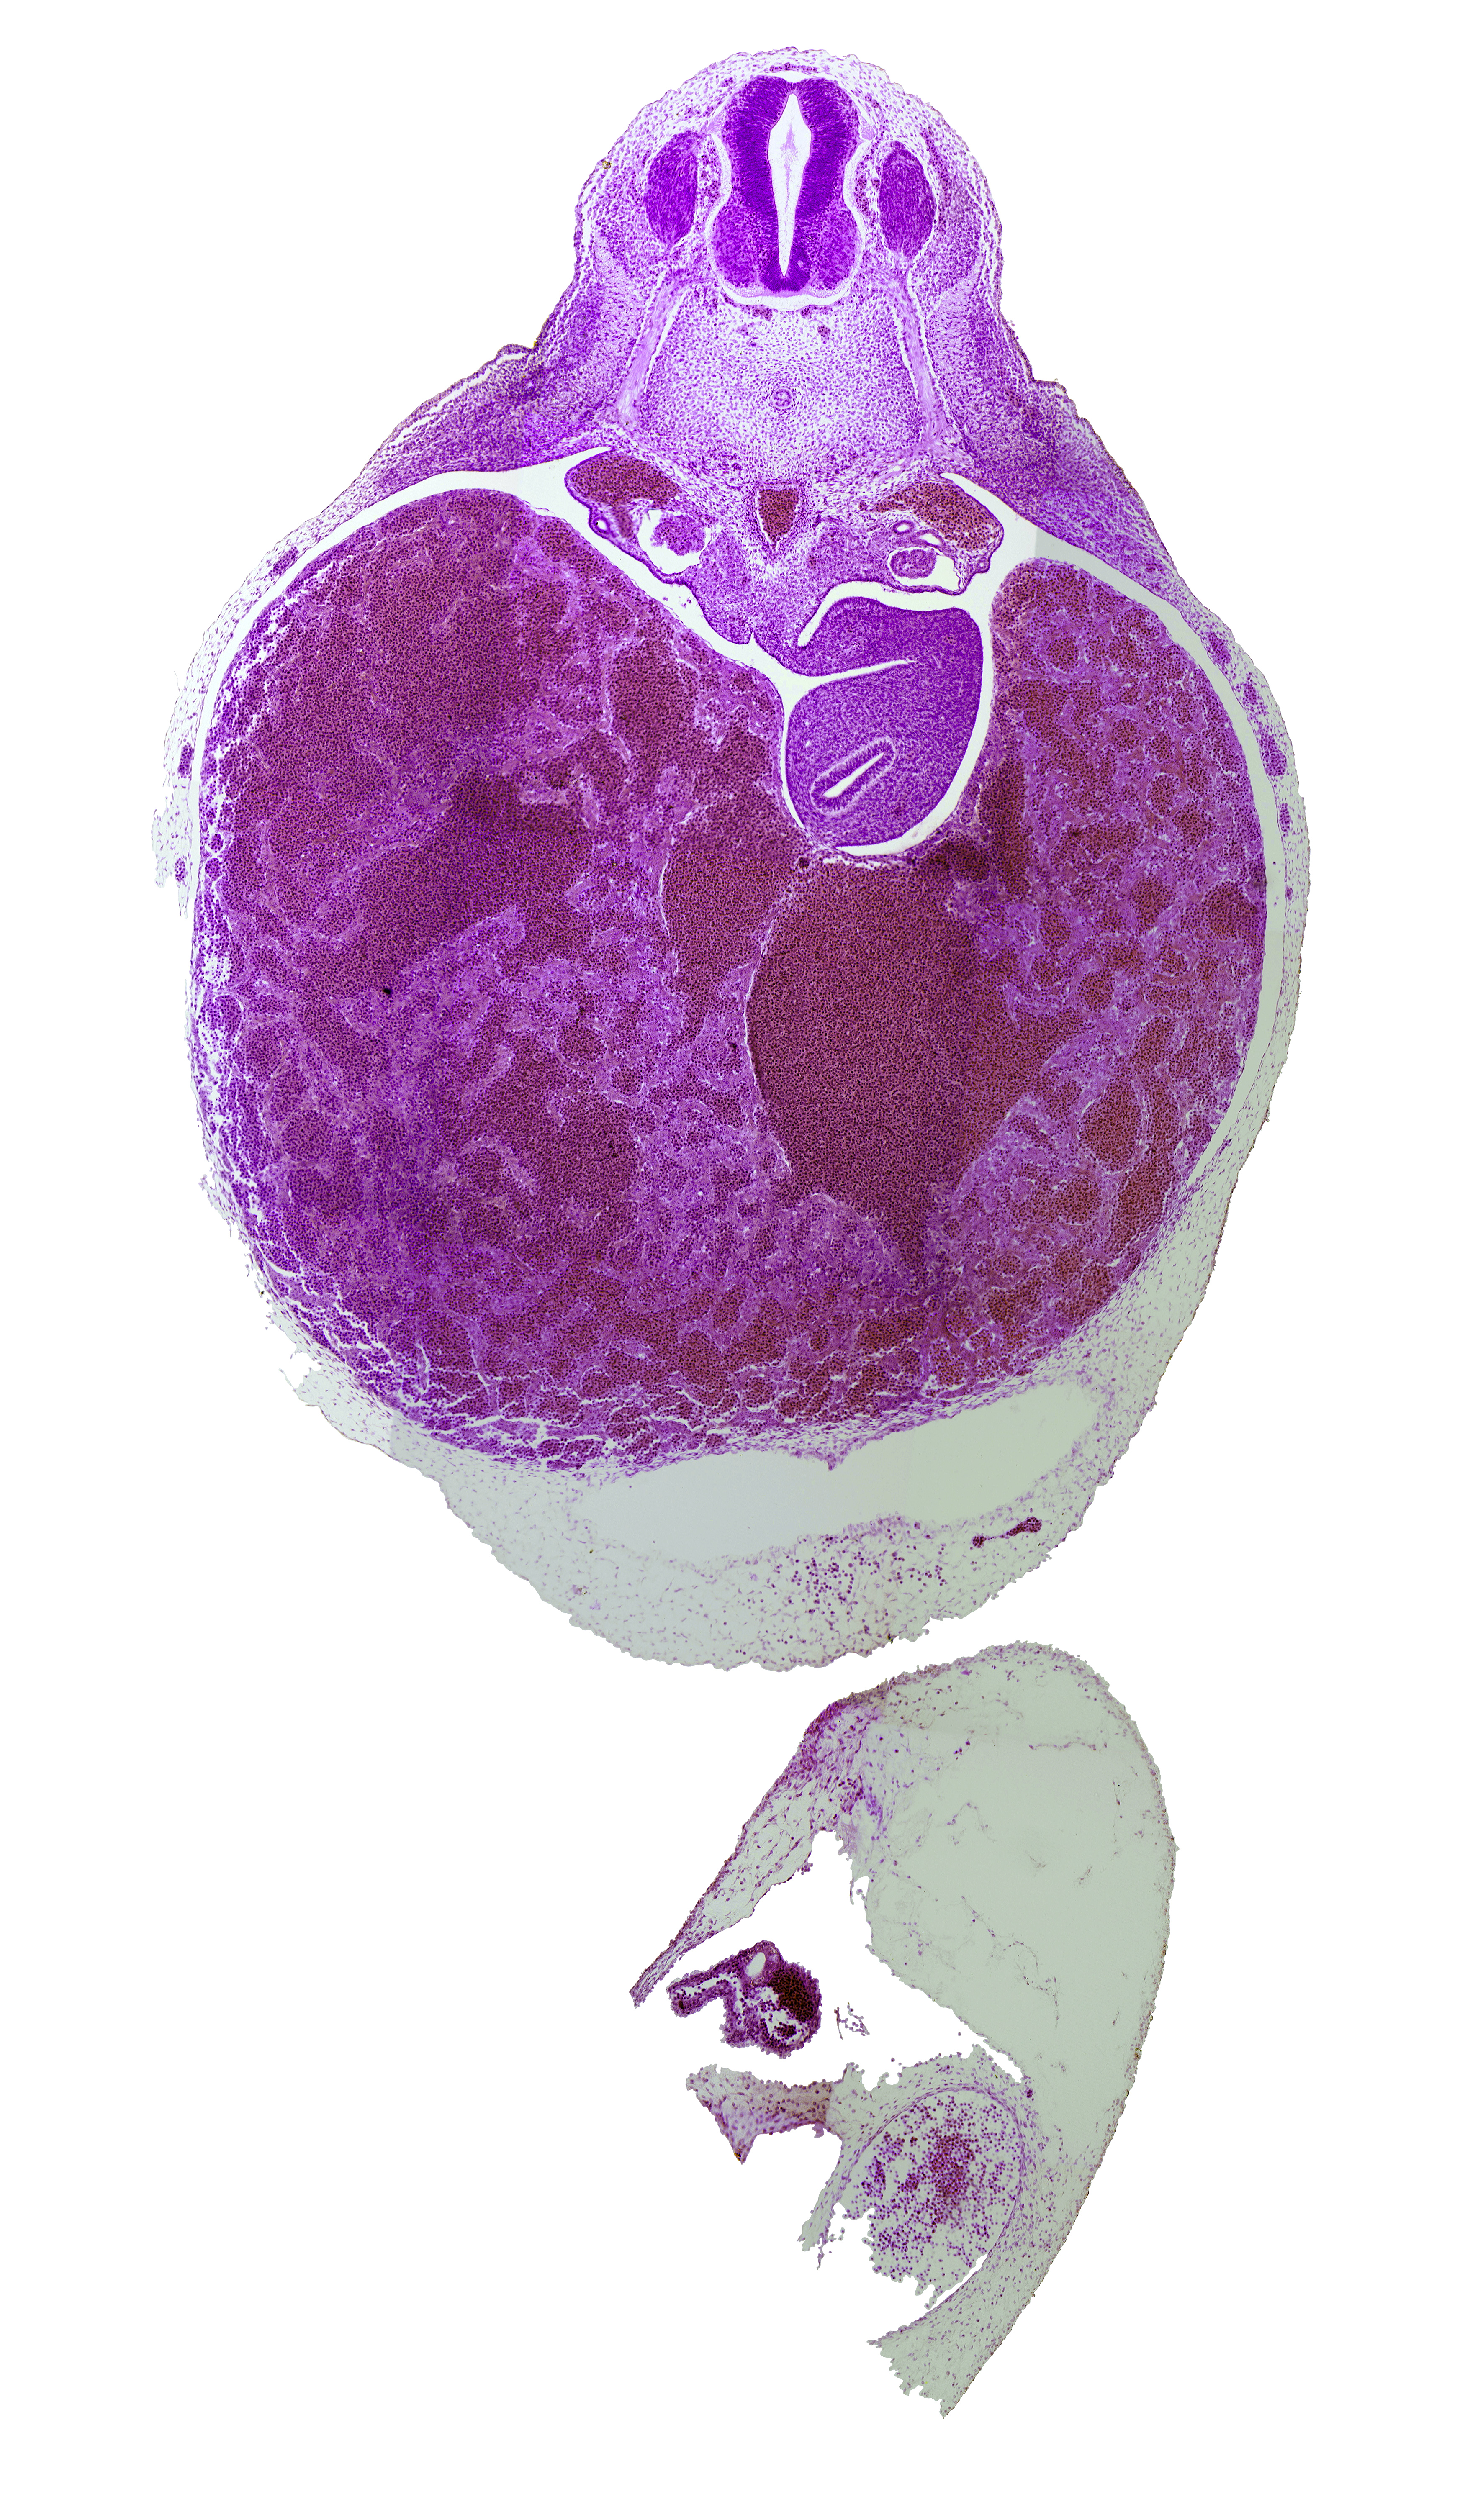

0 μm

Carnegie Embryo #721 | Location: 16-02-01

Keywords: T-3 spinal ganglion, caudal edge of pericardial cavity, ductus venosus, omental foramen, postcardinal vein, splanchnic mesoderm, spleen primordium, stomach endoderm, suprarenal gland primordium

Source: The Virtual Human Embryo.